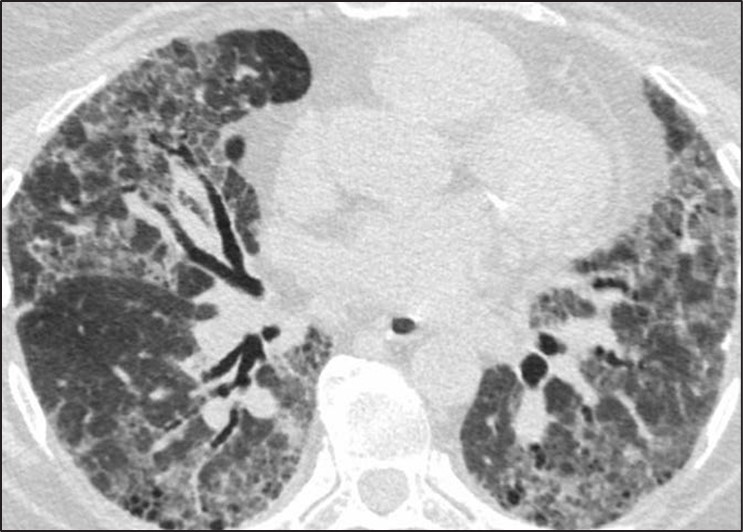

The goals of the radiologist in the evaluation of a patient with suspected pulmonary fibrosis are to determine whether a diffuse lung disease is present, determine the pattern of fibrosis, and provide an appropriate differential diagnosis. Usual interstitial pneumonia (UIP) pattern of pulmonary fibrosis is the most common ILD. UIP is most frequently idiopathic, but can also be secondary to connective tissue disease, medications, or exposure to asbestos [2]. Given the pervasiveness of this diagnosis, radiologists participating in the multidisciplinary diagnosis of patients with suspected ILD are frequently asked whether CT findings support a UIP diagnosis.Fortunately, guidelines can increase the confidence of radiologists in correctly identifying patients with UIP. The American Thoracic Society guidelines for the diagnosis of UIP pattern break down CT findings into four categories: UIP, probable UIP, indeterminate for UIP, and alternative diagnosis. The CT findings indicative of UIP pattern include subpleural and basal predominant fibrosis in addition to honeycombing, with or without traction bronchiectasis (Fig. 1).

Fig. 1—73-year-old man with idiopathic pulmonary fibrosis. HRCT scan shows usual interstitial pneumonia pattern of fibrosis characterized by subpleural and basal distribution of fibrosis with honeycombing.

This is to be distinguished from the probable UIP pattern, which is characterized by the same distribution of fibrosis including reticulation and traction bronchiectasis, but the absence of honeycombing [3].